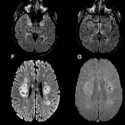

Ilmuan Inggris Peringatkan Adanya Potensi Kerusakan Otak Pada Pasien Covid-19